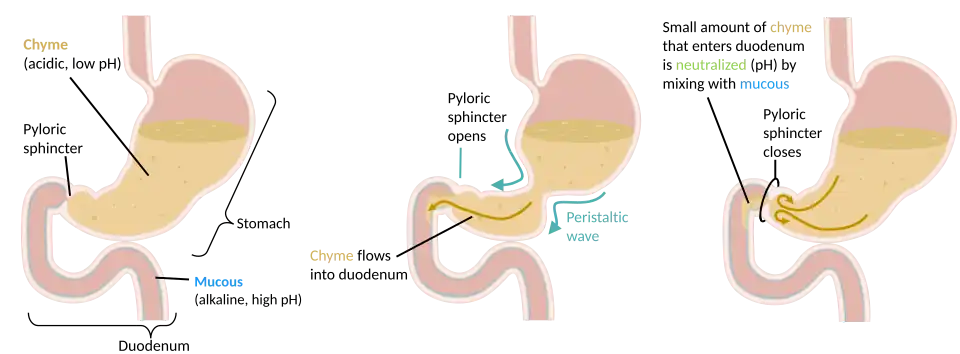

The stomach is located between the esophagus and the small intestine. The pyloric sphincter controls the passage of partially digested food (chyme) from the stomach into the duodenum, the first and shortest part of the small intestine, where peristalsis takes over to move this through the rest of the intestines.

In the human digestive system, a bolus (a small rounded mass of chewed up food) enters the stomach through the esophagus via the lower esophageal sphincter. The stomach releases proteases (protein-digesting enzymes such as pepsin), and hydrochloric acid, which kills or inhibits bacteria and provides the acidic pH of 2 for the proteases to work. Food is churned by the stomach through peristaltic muscular contractions of the wall – reducing the volume of the bolus, before looping around the fundus[33] and the body of stomach as the boluses are converted into chyme (partially digested food). Chyme slowly passes through the pyloric sphincter and into the duodenum of the small intestine, where the extraction of nutrients begins.

Mechanical digestion

Within a few moments after food enters the stomach, mixing waves begin to occur at intervals of approximately 20 seconds. A mixing wave is a unique type of peristalsis that mixes and softens the food with gastric juices to create chyme. The initial mixing waves are relatively gentle, but these are followed by more intense waves, starting at the body of the stomach and increasing in force as they reach the pylorus.

The pylorus, which holds around 30 mL of chyme, acts as a filter, permitting only liquids and small food particles to pass through the mostly, but not fully, closed pyloric sphincter. In a process called gastric emptying, rhythmic mixing waves force about 3 mL of chyme at a time through the pyloric sphincter and into the duodenum. Release of a greater amount of chyme at one time would overwhelm the capacity of the small intestine to handle it. The rest of the chyme is pushed back into the body of the stomach, where it continues mixing. This process is repeated when the next mixing waves force more chyme into the duodenum.

Gastric emptying is regulated by both the stomach and the duodenum. The presence of chyme in the duodenum activates receptors that inhibit gastric secretion. This prevents additional chyme from being released by the stomach before the duodenum is ready to process it.[34]

Control of secretion and motility

Chyme from the stomach is slowly released into the duodenum through coordinated peristalsis and opening of the pyloric sphincter. The movement and the flow of chemicals into the stomach are controlled by both the autonomic nervous system and by the various digestive hormones of the digestive system: